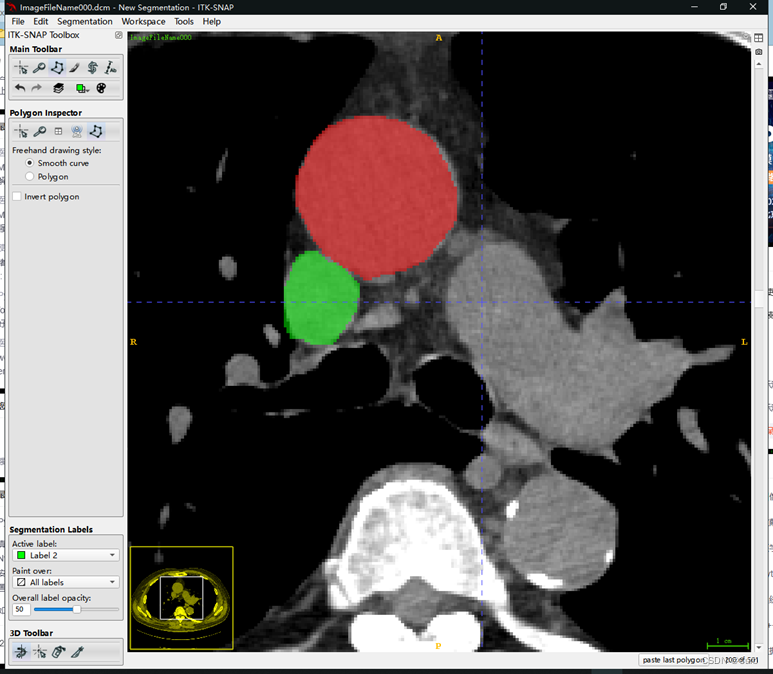

为了方便标注,可以点击上图圈出的位置放大这个方向上的轴向图。效果如下

在这里我连续标注了多张,只选择了两个区域,相当于用了两种标签,效果如下

容易发现三个方向的图都有对应的标签。通过点击下图圈出的update会生成3D的标签图: